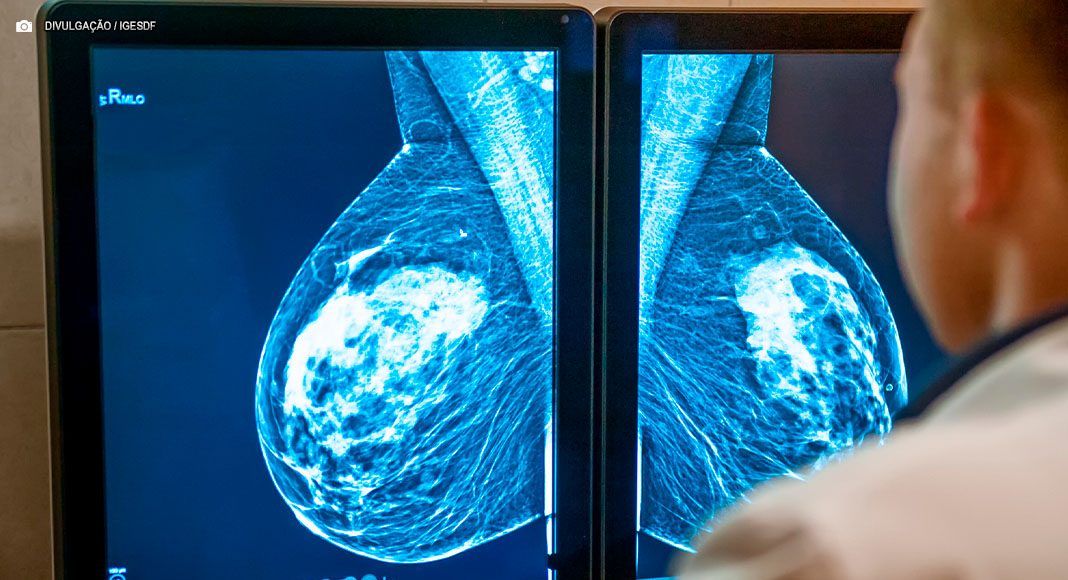

Os dados apontam que os tumores de mama, com 73 mil casos anuais, e de próstata, com 71 mil, lideram as estimativas de incidência, seguidos por cólon e reto, pulmão e estômago. O levantamento destaca ainda a previsão de 483 mil diagnósticos de câncer de pele não melanoma. No Distrito Federal, o cenário epidemiológico acompanha a tendência nacional.

A especialista ressalta que a nova Política Nacional de Prevenção e Controle do Câncer trouxe mudanças nas diretrizes de rastreamento. A ampliação da oferta de mamografia pelo Sistema Único de Saúde (SUS) para mulheres a partir dos 40 anos visa combater o alto índice de acometimento desse tumor.